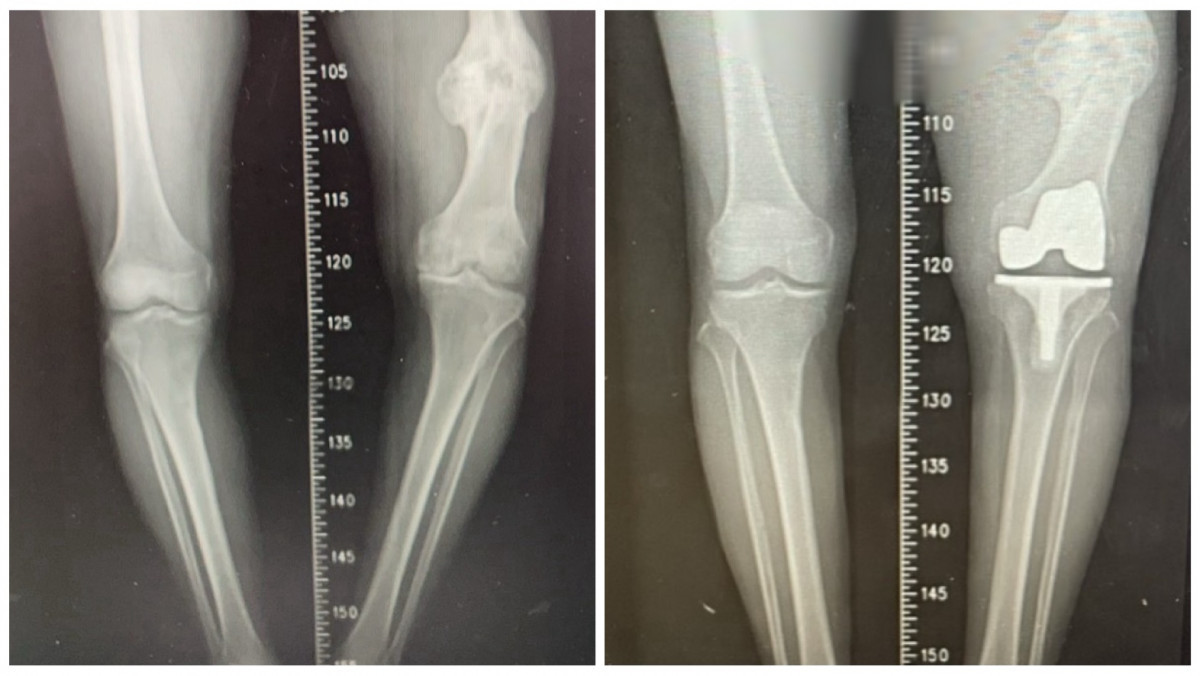

左為術前,右為術後。

台中87歲黃翁年輕時左側股骨骨折,當時治療不佳導致骨癒合不良並出現內翻變形,最初兩下肢僅有約2公分長度差距,隨著時間推移逐漸惡化,最後擴大至近7公分,讓他步態不穩,更引發腰部與下肢不適,長年深受長短腳與膝蓋疼痛所苦。經衛生福利部豐原醫院骨科江福財醫師評估,決定進行人工膝關節置換手術,讓黃先生重拾穩健步伐。

江福財進一步說明,本次手術的困難在於同時面對「陳舊性股骨骨折造成的骨骼變形」與「長達7公分的下肢長度差距」,除進行人工關節置換,還需進行精準的韌帶平衡。江福財解釋,輔以電腦導航與影像輔助技術,得以在修正骨骼角度的同時兼顧關節周圍韌帶平衡,避免造成膝關節不穩定,行動困難,手術並未採用截骨矯正方式,而是單靠人工膝關節置換,直接解決患者最在意的長短腳問題,成功將雙腿長度差縮小至約2.5公分,大幅改善步態。